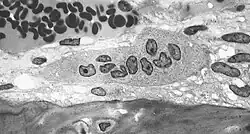

Transmissionselektronenmikroskopische Aufnahme (TEM) eines Osteoklasten in der Bildmitte. Die Mehrkernigkeit dieses knochenabbauenden Zelltyps ist gut sichtbar.

Transmissionselektronenmikroskopische Aufnahme (TEM) eines Osteoklasten in der Bildmitte. Die Mehrkernigkeit dieses knochenabbauenden Zelltyps ist gut sichtbar. -